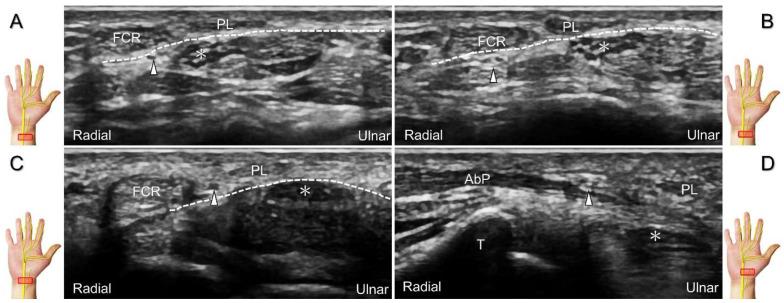

手腕/手部远端周围神经病变的超声成像与引导

超声已成为一种极具价值的工具,用于腕部区域周围神经病变的成像,特别是对于诸如腕管综合征和尺神经管综合征等常见病症。大量研究表明,神经在卡压部位近端肿胀、边界不清和平扁是神经卡压的特征。然而,关于腕部和手部的小神经或终末神经的信息却很匮乏。本文旨在通过全面概述这些神经卡压的扫描技术、病理学和引导注射方法来填补这一知识空白。本综述详细阐述了正中神经(主干、掌皮支和返支)、尺神经(主干、浅支、深支、掌尺皮支和背尺皮支)、桡浅神经、骨间后神经、掌总/指固有神经和背总/指固有神经。一系列超声图像用于详细说明这些技术。最后,超声检查结果补充了电诊断研究,有助于更好地理解整个临床情况,而超声引导下的干预措施对于治疗相关神经病变是安全有效的。